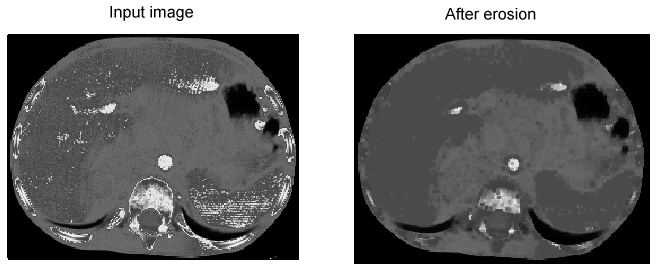

Erosion

Erosion reduces the bright features of the image, which can totally remove noise pixels or small defects:

Image Processing Morphology Theory Grey Scale Morphology Example Erosion

During an erosion operation, the minimum value of all the pixels becomes the grey value in the output image at the pixel corresponding to the center of the structuring element. A dilation operation takes the opposite approach, using the maximum value for the output image.